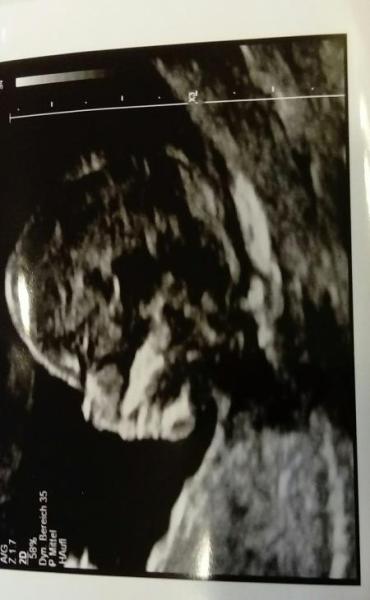

So endlich mal Zeit :) Bei mir wurde heute ein sehr genauer Ultraschall gemacht und da sieht alles super aus und der Wert der zu niedrig ist nun ja er ist ein bisschen zu niedrig und ich könnte jetzt weiter machen mit Biopsie und so aber das möchten wir nicht! Er hat uns gut beruhigt

Bild zu